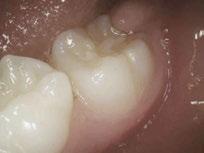

Kidstown Dental often consults for “re-treat” on poorly done or reattached tongue ties. Dr. Amy shares a sweet email from a patient who had received a frenectomy in another practice with a laser that does not use water and works with heat. The family came to Dr. Amy months after the surgery, thinking they needed a second surgery because the child was still suffering with feeding, speech, and sleep. Dr. Amy did three of the non-surgical treatments of LAFTR paired with interdisciplinary bodywork and functional help, and they were able to achieve life-changing results without any further surgery. Now, he is 3 years old and is sleeping and eating normally and speaking in full sentences. Dr Amy shares, “Only a few years ago, this child would have likely ended up with multiple surgeries, increasing the risk of scar tissue, oral aversions, and trauma, and still end up in a variety of therapies, like speech and occupational therapy. I am so glad we can finally help families with this simple, elegant, yet powerful laser intervention.”

Dr. Amy explains how to avoid a surgery if the child has signs of tongue tie and even the look of a posterior tongue tie. “Sometimes a frenum can look short and tight, and the patient may present with a lot of tongue-tie symptoms, but it may not actually be a true physical restriction. LAFTR is a great tool to use for differential diagnosis, particularly of posterior tongue tie. For example, the genioglossus muscles are airway dilator muscles under the tongue, and the frenum lays just over these muscles with lots of fascia connected to and around it. When patients have an airway issue, their genioglossus muscles are going to be contracting to dilate that airway open, and the frenum will be necessarily shortened artificially. So a short frenum on the initial exam may be indicative of an airway challenge. When the patient’s frenum is cut, the body will generally form the new frenum to be just as short and tight as the previous frenum, and then it often gets classified as ‘reattached.’ But LAFTR instantly releases all the artificial tension in the fascia, making it supple, and sometimes the frenum will lengthen 2-3 times compared to how it appeared on initial exam. A true physical restriction of the lingual frenum doesn’t lengthen because the fibers of a true tongue tie are different from simple fascia in a normal frenum. This is why we use this tool prior to any non-reversible cutting procedures.”

cutting the fibers of the frenum, you’ll be cutting fascia around it too to get the full range of motion. “Using the laser in the LAFTR protocol, which we do for every single frenectomy in 5 minutes, we are able to get the frenum clearly visible, releasing the other tensions non-surgically around it, for a faster, easier, more effective, and more comfortable frenectomy surgery.”